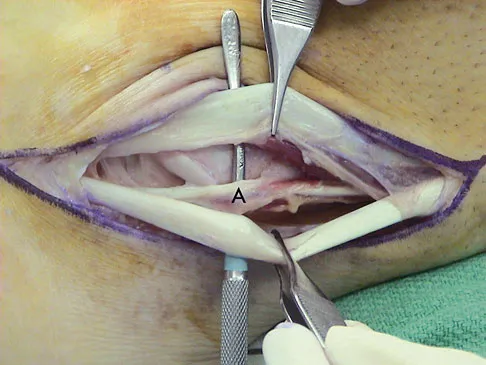

Question 81

A 35-year-old man is seen for evaluation of his left ankle following multiple previous ankle sprains and frequent episodes of the ankle giving way. Examination reveals marked laxity about the lateral ankle with associated tenderness along the peroneal tendons. Physical therapy, anti-inflammatory drugs, and supportive bracing have failed to provide relief. An MRI scan shows peroneal tenosynovitis and a possible tear. He elects to undergo a peroneal tendon repair and lateral ligament reconstruction. Which of the following best describes the structure labeled "A" in Figure 45?

Explanation